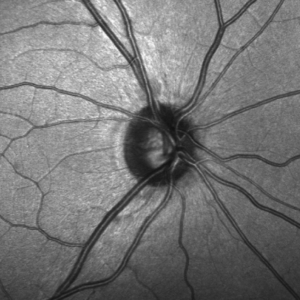

Imagen del nervio óptico registrada con un tomógrafo de coherencia óptica

El glaucoma es una enfermedad ocular que se caracteriza por la pérdida de visión como consecuencia de un daño irreversible en el nervio óptico, provocada generalmente por un aumento de la presión intraocular.